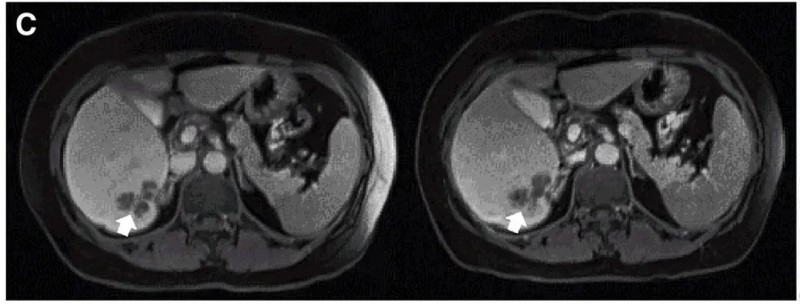

值得一提的是,典型病例P10患者在接受DL4剂量CEACAR-T治疗后,MRI证实其肝内一处病灶明显缩小,左图为治疗前影像,右图为治疗4周后影像对比。

▲图源“Molecular Therapy”,版权归原作者所有,如无意中侵犯了知识产权,请联系我们删除